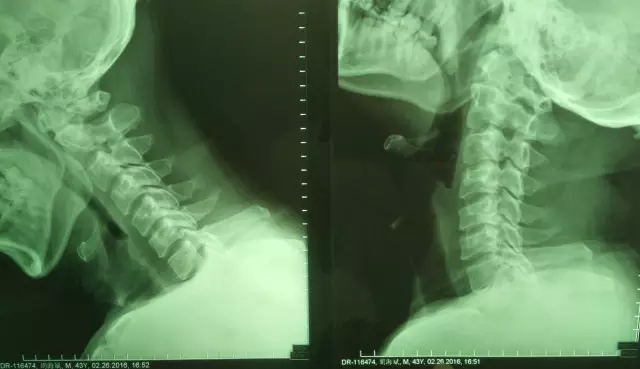

當(dāng)天接診的正是廣安醫(yī)院副院長、脊柱外科主任劉志安。聽完胡先生受傷的經(jīng)過,劉志安懷疑患者的頸椎可能受到傷害。于是讓他做了核磁共振(MRI),經(jīng)MRI診斷為:①頸椎過伸傷 ②頸脊髓損傷伴上肢不全癱 ③頸椎間盤突出癥,必須手術(shù)治療。隨后,劉志安將診斷結(jié)果告訴胡先生,并與他商定了治療方案。

“頸椎過伸性損傷是頸椎過度伸展性暴力造成的頸脊髓損傷,通常有較輕微或隱匿的骨損傷,X線多無異常征象,故而易被疏漏,影響治療。這種損傷并不少見,并常常合并脊髓中央綜合征,且多見于中老年人。”劉志安解釋道,“其發(fā)生情況多系來自面頜方向的暴力。主要是上肢重于下肢的四肢癱、感覺分離及頸部癥狀。X線平片、MRI和CT檢查能明確診斷。”